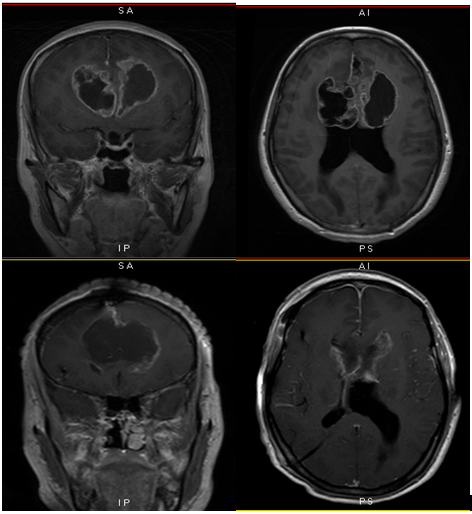

入院后颅脑MRI提示:双侧额叶跨胼胝体占位性病变,考虑胶质母细胞瘤可能性大,合并双侧侧脑室梗阻性脑积水。转神经外二科治疗,复查头颅CT提示脑积水较前略加重,考虑到患者颅高压症状较明显,肿瘤压迫及脑积水加重所致,不排除颅压进一步增高导致患者昏迷甚至呼吸停止可能,遂急诊行脑室外引流术,术后给予综合观察治疗,为手术切除完善术前准备。同期,行全麻下双侧额叶及胼胝体高级别胶质肿瘤切除术+ICP探头植入术,手术由神经外二科主任林涛主刀完成,切除肿瘤大小约:6.0*5.5*4.0cm,双侧大脑前动脉保护良好。术后查体:神清,对光反射灵敏,心肺腹未见异常,肌张力正常。考虑恶性较高胶质瘤,故后续仍需放化疗治疗。